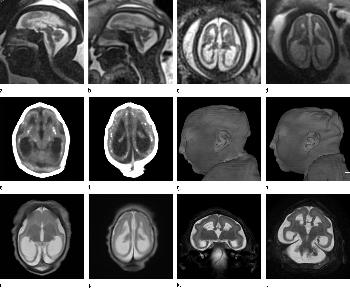

Figure 2. (a) Axial, (b) sagittal, and (c) coronal fetal T2-weighted MR images were obtained in a 29-year-old woman with confirmed Zika virus infection, initially seen for characteristic rash at 12 weeks of gestational age. (d) Axial postnatal CT image and (e–g) axial and (h) coronal T2-weighted MR images were obtained in her male neonate. The fetal MR images obtained at 34 weeks (a–c) show asymmetrical ventriculomegaly with a septation in the right occipital horn (arrowhead on a), small frontal lobes, thinning of the occipital parenchyma (left worse than right), underdeveloped sylvian fissures, and regions of thickened cortex, as in the right frontal lobe, which is suggestive of polymicrogyria (arrow on a). There is abnormal, increased signal intensity in the white matter. The postnatal CT image (d) obtained in the 22-day-old neonate shows punctate calcifications at the gray matter–white matter junction and asymmetrical ventriculomegaly. The T2-weighted MR images obtained at 26 days (e–h) show septation in the ventricle (arrowhead on e). Note how the right ventricle has relatively decreased in size compared with the prenatal image, whereas the left ventricle has increased in size. Under-rotation of the hippocampus (arrowheads on f) is demonstrated. There is clear asymmetry of the gyral pattern on g, which is relatively smooth in the left occipital region, with abnormal folds in the right occipital and frontoparietal regions (arrows on g). Subependymal cysts are visualized on h, which are not seen on fetal MR images.

Figure 3. Images obtained in the case of a 34-year-old woman with confirmed Zika virus infection, initially seen for a rash at 8 weeks of gestation. Fetal head cir¬cumference was in the normal range at 12 and 16 weeks (5.8 cm and 11.9 cm, respectively) but then decreased to the 10th percentile at 22 weeks and was below the 3rd percentile in subsequent imaging examinations. (a–h) US images were obtained at 30 weeks. Head circumference on the axial image (a) measured 24 cm (˂2.3 percentile, corresponding to a gestational age of 26 weeks 3 days). Note the open sylvian fissures and relatively smooth cortex, which are abnormal findings at this gestational age. Oblique axial image (b) shows cerebellar calcifications (seen as the echogenic outer contour of the cerebellar hemispheres) and inferior vermian hypoplasia with associated enlarged cisterna magna. A sagittal transvaginal image (c) shows calcifications in the basal ganglia (arrowheads) and more bulky calcifi¬cation at the gray matter–white matter junction. Another sagittal transvaginal image (d) shows a relatively small corpus callosum (arrows). A coronal image (e) shows cortical and subcortical white matter calcifications in a linear pattern. The gyral pattern is abnormal, which is suggestive of polymicrogyria. A sagittal Color Doppler image (f) shows a stretched appearance of vessels coursing into the posterior fossa. An oblique axial grayscale transvaginal image in the posterior fossa (g) shows heterogeneous material in the confluence of sinuses due to blood clot (arrow). A three-dimensional US image of the face (h) shows a sloping forehead, compatible with frontal lobe hypoplasia. (i) Axial and (j) sagittal fetal MR images obtained at 29 weeks show atrophic frontal lobes, wide sylvian fissures, enlarged posterior fossa, abnormal gyral pattern, prominent cerebrospinal fluid spaces, and inferior vermian hypoplasia. On (i), note the diffuse hypointense and undersulcated cortex, which is suggestive of mineralization and polymicrogyria. The hypoplastic corpus callosum can be seen on the sagittal view (j), as well as the inferior vermian hypoplasia, en¬larged cisterna magna, and heterogeneous signal intensity in the confluence of sinuses. There is a subjectively thin spinal cord. (k) Postnatal axial MR image obtained at 81 days shows small frontal lobes and cortical thickening. The choroid plexi are enlarged. (l) Photograph of the neonate after birth.

Figure 4. Images obtained in the case of an 18-year-old woman, first seen for rash at 10 weeks of pregnancy, with confirmed Zika virus infection. US findings obtained at 20 weeks of gestational age were reportedly normal, with normal head circumference of 17.5 cm. At 37 weeks of gestational age, (a) sagittal transvaginal and (b) coronal transabdominal US images obtained with the head upside down show a small head circumference (26.4 cm, corresponding to 28 weeks 5 days, below the 3rd percentile), moderate ventriculomegaly with dense intracranial calcifications (arrowheads on a), and abnormal head shape with flattened appearance and thickened skin (arrow on a). On the sonogram, it is difficult to precisely localize the calcifications, given the thin parenchyma. (c, d) Axial bone window CT images, (e) sagittal localizer CT image, and (f–h) axial CT images show microcephaly with cerebral atrophy, and, despite ventriculomegaly, the extra-axial cerebrospinal fluid spaces are still prominent. The hypoattenuating calcifications are predominantly located in the subcortical white matter at the gray matter–white matter interface. There is markedly abnormal skull shape with some eversion of the bones at the suture sites (particularly frontoparietal sites), with redundant skin folds (particularly in the parieto-occipital region). (i) Sagittal T1-weighted, (j, k) coronal T2-weighted, and (l) axial susceptibility-weighted MR images obtained at 1 month of age show an undersegmented midbrain, severe microcephaly, open sylvian fissures, and polymicrogyria. The dense calcifications are evident on the susceptibility-weighted image. On the sagittal images (a, e, i), note the small supratentorial compartment and associated skull deformity.

Figure 5. Images obtained in the case of a 33-year-old woman who had a rash at 10 weeks of pregnancy, with confirmed Zika virus infection. US performed at 19 weeks of gestational age showed a head circumference in the normal range (16.6 cm). (a, b) Sagittal and (c) coronal transvaginal US images obtained at the next US examination at 27 weeks 2 days of gestational age, however, showed the fetal head circumference to be 21.6 cm, which corresponded to 23 weeks 3 days (˂2.3 percentile, not shown). There was mild ven¬triculomegaly with septations in the occipital horns. Calcifications could be seen at the gray matter–white matter junction. The cerebrum was atrophic. There was blood clot in the region of the confluence of sinuses (arrow on c). (d) Coronal, (e) axial, and (f) sagittal T2- weighted fetal MR images obtained at 32 weeks show septations in the ventricles and an abnormal-appearing cortex, with a thickened and undersulcated cortex most marked on the left, compatible with polymicrogyria. The sagittal midline view shows microcephaly, blood clot in the region of the confluence of sinuses, and prominent skin folds. (g, h) Axial T2-weighted and (i) sagittal T1-weighted postnatal MR images obtained in the 4-week-old neonate show diffuse gyral abnormality and abnormal myelination. The septations in the ventri¬cles are again seen. The sagittal image shows thinning of the spinal cord at the craniocervical junction.

Figure 6. Images obtained in the case of a 24-year-old woman pregnant with twins, with characteristic rash at 9 weeks of pregnancy and confirmed Zika virus infection. (For each pair of images, the first image is of twin A, and the second image is of twin B.) At 14 weeks of gestational age, the fetal head size of both twins was normal. The head size never went below the 3rd percentile for either fetus in examinations at 19–28 weeks. (a, b) Sagittal and (c, d) axial fetal MR images were obtained at 36 weeks. (e, f) Axial and (g, h) surface reconstruction postnatal CT images and (i, j) axial T2-weighted and (k, l) coronal MR images were obtained 1 week after delivery at 38 weeks of gestational age. There is severe microcephaly with profound frontal lobe hypoplasia. Calcifications in the subcortical white matter at the gray matter–white matter junction are visualized. Both twins have a flattened appearance of the pons. The spinal cord is atrophic (best seen on a). Redundant skin is seen in the occipital region. There is polymicrogyria involving the frontal and parietal regions and atrophic cortex and white matter in the occipital regions. Each twin has hypoplasia of the corpus callosum, with prominent fornices. There is abnormal myelination in the occipital region that, in twin A (i), has the appearance of a cyst or septation within the ventricle. The cerebellum is somewhat small and nodular. There is lack of rotation of the hippocampi.